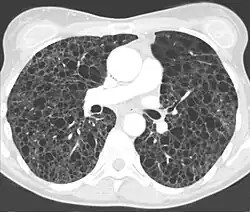

Die eindeutige Diagnose ist mittels Computertomographie oder durch eine Lungenbiopsie möglich. Der CT-radiologische Befund[7] ist typisch und erlaubt in aller Regel die Diagnosestellung.

- ↑ G. F. Abbott, M. L. Rosado-de-Christenson, A. A. Frazier, T. J. Franks, R. D. Pugatch, J. R. Galvin: From the Archives of the AFIP: Lymphangioleiomyomatosis: Radiologic-Pathologic Correlation. In: Radiographics. 25, 2005, S. 803–828, doi:10.1148/rg.253055006.